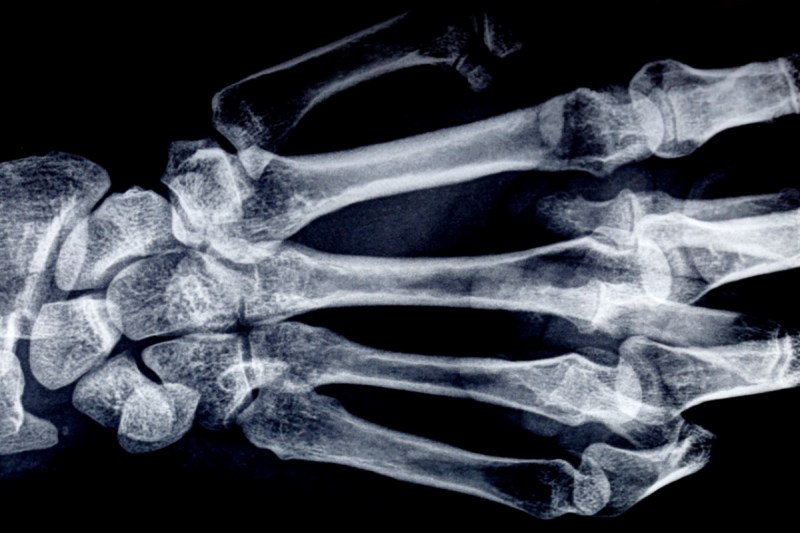

“A little bit of skeleton for Halloween — my own newly renovated left hand,” the 70-year-old author wrote on October 28 alongside an image of a gnarly X-ray of her hand. “No, I cannot flick out that claw like Wolverine; it stays on the inside for good. (Probably for the best; my “berserkers” come on when I read the daily news.)”

Surgery for the condition usually involves an orthopedic hand surgeon removing the thick, tight fascia tissue in the palm. This procedure, known as a fasciectomy, restores finger movement and allows them to straighten. In Kingsolver’s case, it also appears to have involved inserting metal pieces to support her pinky.

“Arthrodesis,” she began in the explanation of her procedure. “It’s a last resort, if a finger keeps curling closed to the palm after multiple release surgeries. With luck, you won’t ever need it. (My case is extreme.) The hardware fixes it permanently in a semi-open position. Joints no longer work, but you get open-hand function back.”